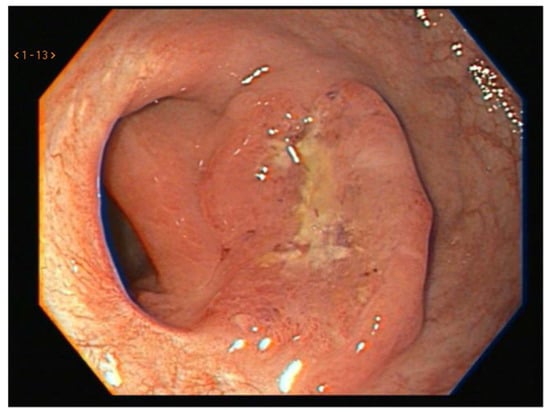

5.2. Three-Pillar Assessment Criteria

- Habr-Gama, A.; Perez, R.; Wynn, G.; Marks, J.; Kessler, H.; Gama-Rodrigues, J. Complete clinical response after neoadjuvant chemoradiation therapy for distal rectal cancer: Characterization of clinical and endoscopic findings for standardization. Dis. Colon Rectum 2010, 53, 1692–1698. [Google Scholar] [CrossRef]

- Maas, M.; Lambregts, D.M.J.; Nelemans, P.J.; Heijnen, L.A.; Martens, M.H.; Leijtens, J.W.A.; Sosef, M.; Hulsewé, K.W.E.; Hoff, C.; Breukink, S.O.; et al. Assessment of Clinical Complete Response After Chemoradiation for Rectal Cancer with Digital Rectal Examination, Endoscopy, and MRI: Selection for Organ-Saving Treatment. Ann. Surg. Oncol. 2015, 22, 3873–3880. [Google Scholar] [CrossRef] [PubMed]

- Custers, P.A.; Geubels, B.M.; Beets, G.L.; Lambregts, D.M.J.; E van Leerdam, M.; van Triest, B.; Maas, M. Defining near-complete response following (chemo)radiotherapy for rectal cancer: Systematic review. Br. J. Surg. 2022, 110, 43–49. [Google Scholar] [CrossRef]